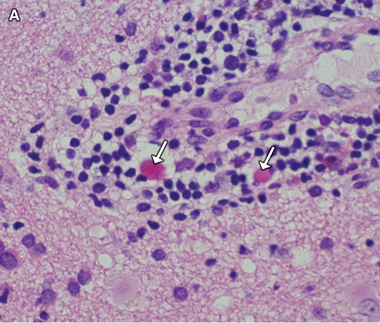

A diagnosis of West African trypanosomiasis was considered, but peripheral blood and lymph node tissue were negative for trypanosomes; lumbar puncture was not performed because of concern about increased intracranial pressure. Because of a rapid deterioration in the patient’s condition and the continuing uncertainty over the diagnosis, a stereotactic brain biopsy was performed. Histological examination of the biopsy specimen showed meningoencephalitis with Mott (morula) cells (Box 3A), suggesting human African trypanosomiasis (HAT). Review of the previous CSF cytology specimens also revealed Mott cells (Box 3B), which had not been recognised initially. Indirect haemagglutination tests of serum for HAT-specific antibodies gave positive results, with a titre of 1:4096.

Non-specific CNS findings are meningoencephalitis, comprising leptomeningitis and encephalitis with diffuse perivascular white matter infiltration, microglial nodules and reactive astrocytosis.8 The presence of Mott cells in the CNS and CSF is characteristic of HAT, but these cells are easily overlooked.9 They are morula forms of plasma cells containing prominent eosinophilic cytoplasmic inclusions (Russell bodies) that stain positively with periodic acid-Schiff stain and are composed of immunoglobulin M. Although Mott cells can be found in myeloproliferative disorders, they are considered virtually pathognomonic of HAT in patients with appropriate clinical findings and exposure history.10